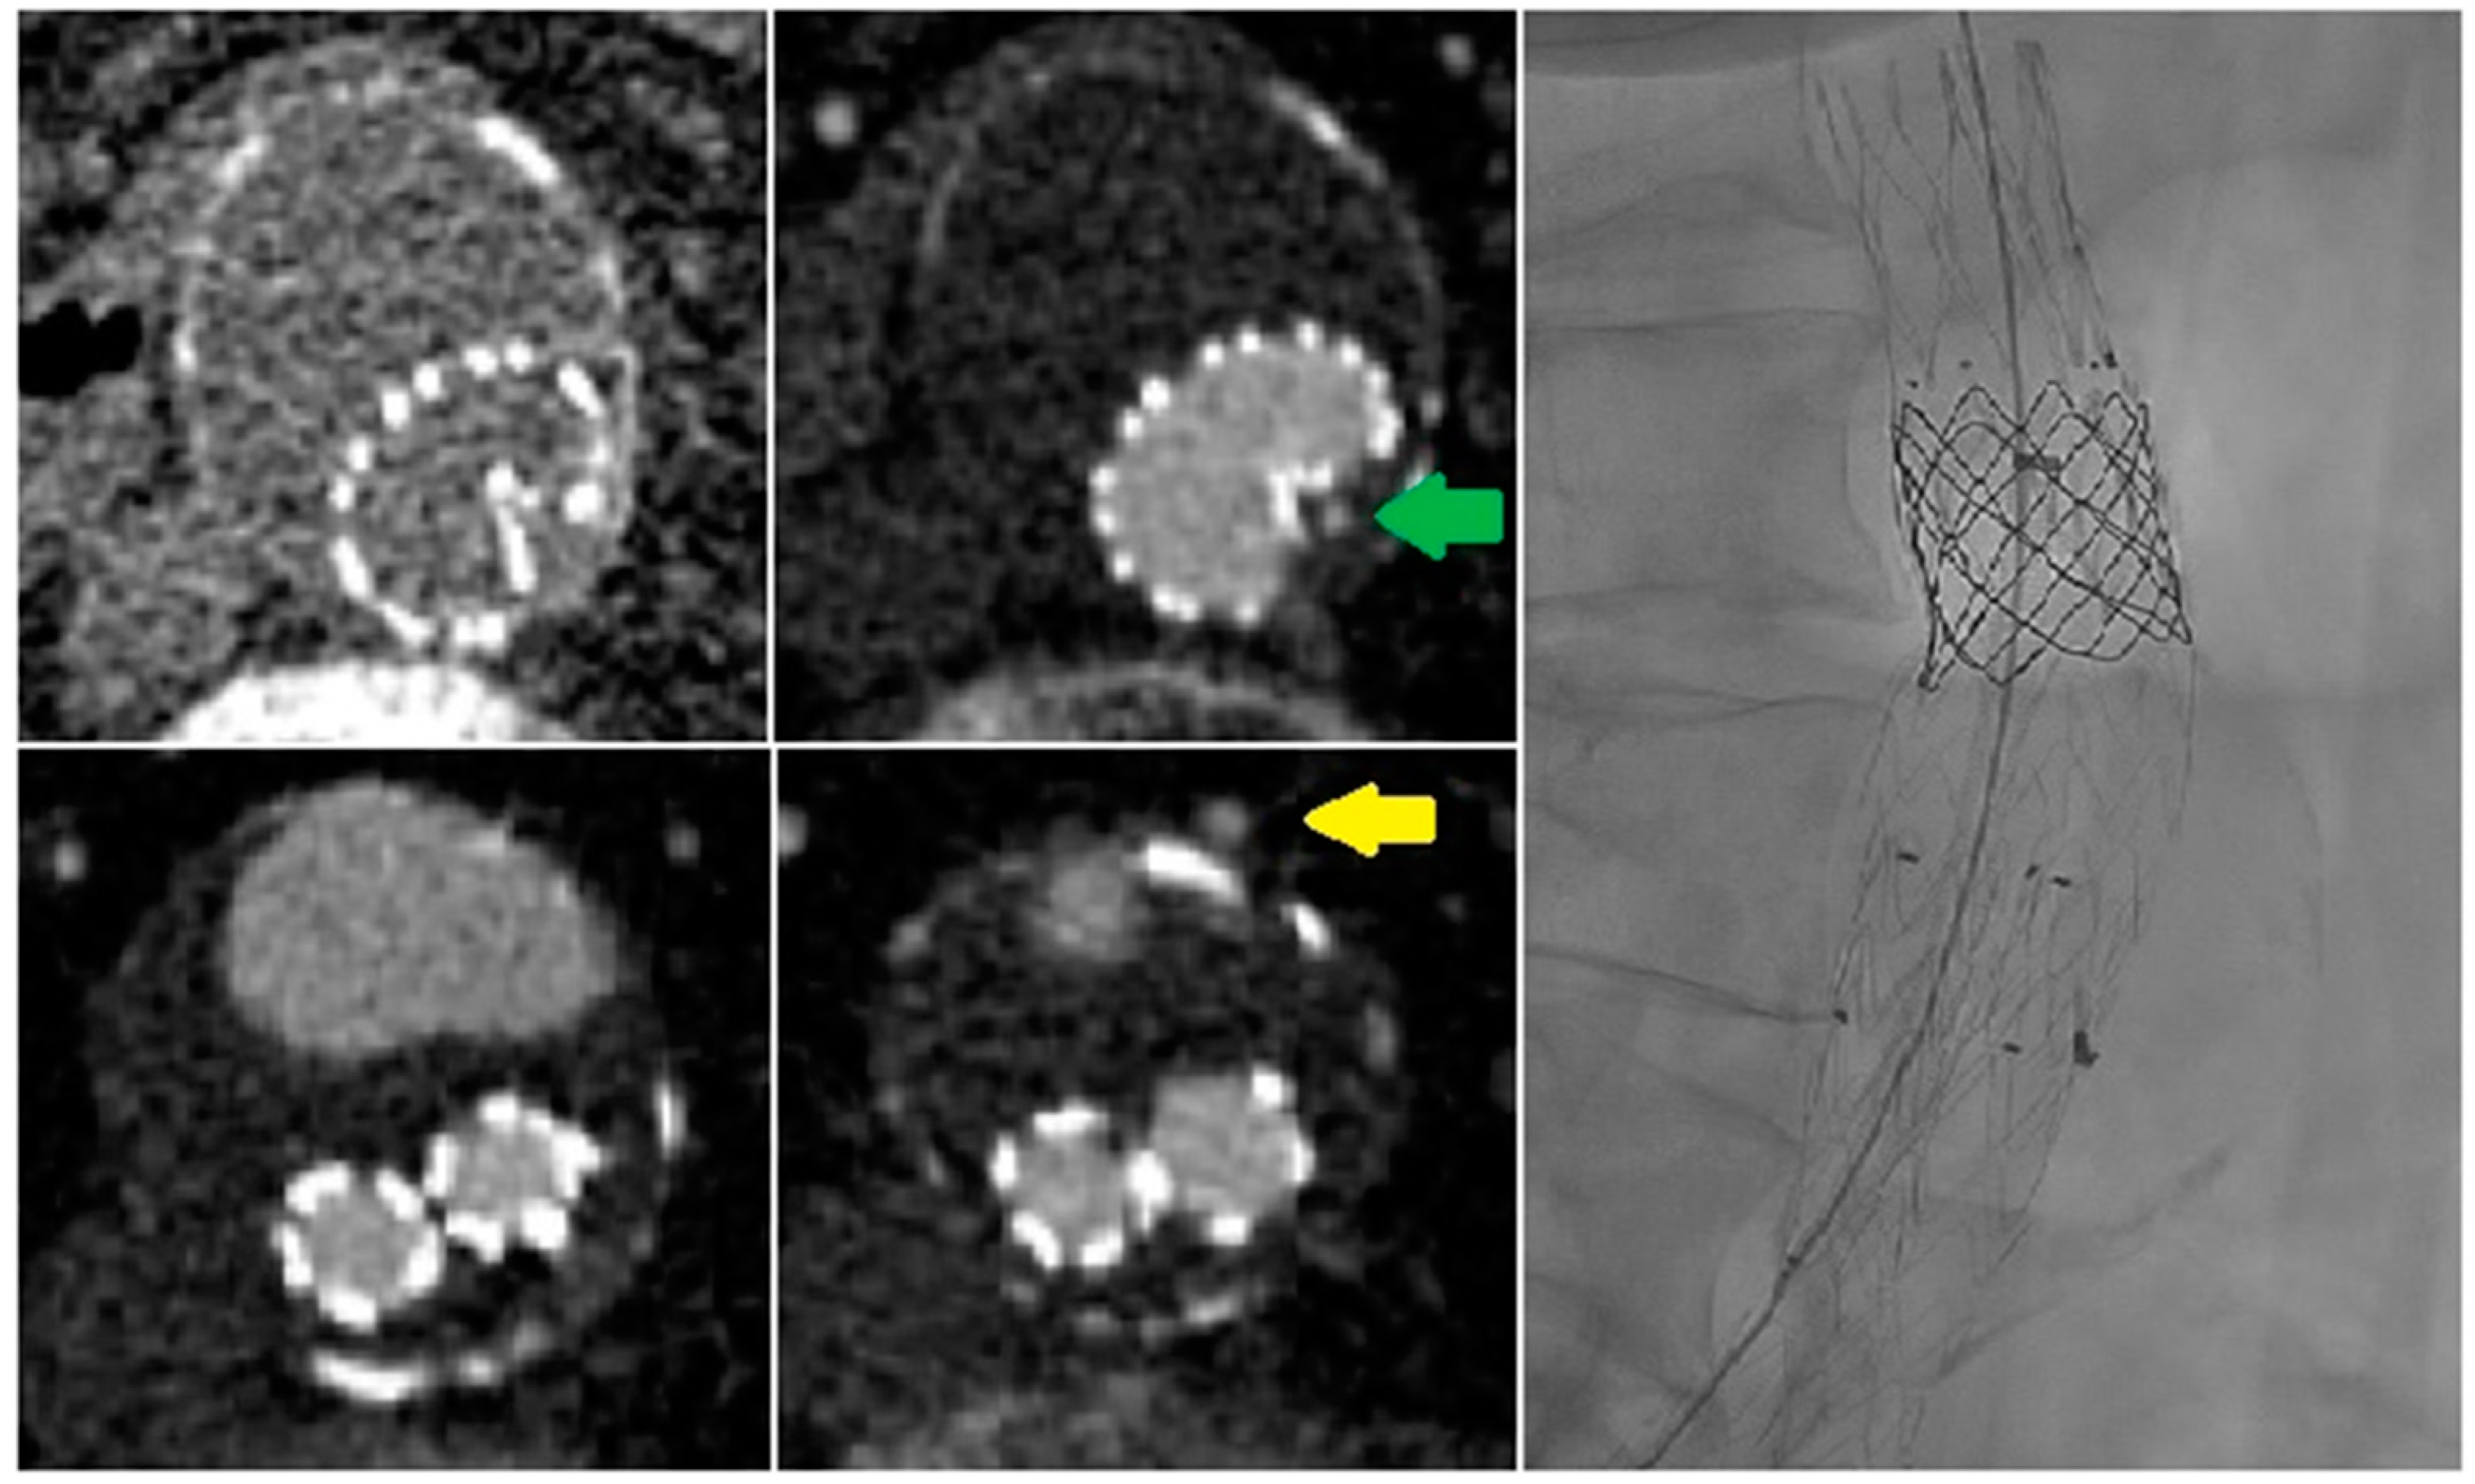

4.1. Time Attenuation Curves

| Patient No. | Age (Years) | Sex | Initial Diameter (mm) | Diameter Increase (mm) | Time after Initial Operation (months) | Endoleak Classification on sCTA | Indication for dCTA | Endoleak Classification on dCTA |

|---|---|---|---|---|---|---|---|---|

| 1 | 78 | Male | 58 | +1 | 18 | 1× type II, 1× undefined | Undefined EL (type Ia or II) | 2× type II |

| 2 | 77 | Male | 56 | +20 | 39 | 1× undefined | Undefined EL (type Ia or II) | 1× type II |

| 3 | 88 | Male | 57 | +10 | 129 | None | AAA diameter increase without an endoleak | 1× type IIIb |

| 4 | 84 | Male | 59 | +10 | 54 | 1× undefined | Undefined EL (type Ia or II) | 1× type II |

| 5 | 83 | Female | 57 | +8 | 9 | 1× undefined | Undefined EL (type Ia or II) | 1× type IIIb |

| 6 | 87 | Male | 59 | +7 | 81 | 1× type II | AAA diameter increase with unclear origin of type II EL | 2× type II |

| 7 | 74 | Male | 74 | +8 | 85 | 1× type II | AAA diameter increase without an endoleak | 2× type II |

| 8 | 84 | Male | 59 | +1 | 62 | 1× undefined | Undefined EL (type Ib or II) | 3× type II |

| 9 | 67 | Male | 38 | +8 | 34 | 1× type II | AAA diameter increase with unclear origin of type II EL | 1× type II |

| 10 | 78 | Male | 57 | None | 15 | 1× undefined | Undefined EL (type Ia, II or III) | 1× type II |

| 11 | 66 | Male | 53 | +3 | 3 | 1× undefined | Undefined EL (type II or III) | 1× type II |

| 12 | 89 | Female | 54 | +12 | 93 | None | AAA diameter increase without an endoleak | None |

| 13 | 73 | Male | 62 | +8 | 25 | 1× undefined | Undefined EL (type II or III) | 1× type II |

| 14 | 83 | Male | 56 | +6 | 35 | 1× undefined | Undefined EL (type Ia or II) | 1× type II |

| 15 | 73 | Female | 54 | None | 8 | 1× undefined | Undefined EL (type Ia or II) | 1× type Ia |

| 16 | 66 | Male | 49 | +2 | 74 | 1× undefined | Undefined EL (type II or III) | 1× type IIIb |

| Patient No. | Endoleak | Branch | Peak Stent (HU) | Peak Endoleak | Peak Endoleak/ Stent (%) | Time Peak Stent (s) | Time Peak Endoleak (s) |

|---|---|---|---|---|---|---|---|

| 1 | 2× type II | AMI | 348.8 | 332.4 | 95.3 | 20.6 | 28.9 |

| L1 | 348.8 | 333.6 | 95.6 | 20.6 | 28.6 | ||

| 2 | 1× type II | L1 | 370.9 | 304.1 | 82 | 28.5 | 33.3 |

| 3 | 1× type IIIb | 459.9 | 425.8 | 92.6 | 25.6 | 28.9 | |

| 4 | 1× type II | L1 | 401.2 | 252.1 | 62.8 | 23.6 | 33.4 |

| 5 | 1× type IIIc | NA | NA | NA | NA | NA | |

| 6 | 2× type II | AII | 607.4 | 268.3 | 44.2 | 33.4 | MAX * |

| L1 | 607.4 | 323.6 | 53.3 | 33.4 | MAX * | ||

| 7 | 2× type II | L1 | 538.9 | 186.6 | 34.6 | 28.6 | MAX * |

| L2 | 538.9 | 171 | 31.7 | 28.6 | MAX * | ||

| 8 | 3× type II | AMI | 496.1 | 350 | 70.6 | MAX * | MAX * |

| L1 | 496.1 | 341.7 | 68.9 | MAX * | MAX * | ||

| L2 | 496.1 | 138.8 | 28 | MAX * | MAX * | ||

| 9 | 1× type II | L1 | 549.9 | 232.6 | 42.3 | 23.5 | 33.5 |

| 10 | 1× type II | NA | NA | NA | NA | NA | NA |

| 11 | 1× type II | NA | NA | NA | NA | NA | NA |

| 12 | None | NA | NA | NA | NA | NA | |

| 13 | 1× type II | L1 | 473.1 | 413 | 87.3 | 24.2 | 30.5 |

| 14 | 1× type II | L1 | 306.1 | 78.1 | 25.5 | 30.8 | 38.5 |

| 15 | 1× type Ia | 466 | 408.6 | 87.7 | 18.8 | 23.7 | |

| 16 | 1× type IIIb | 473.1 | 413.4 | 87.4 | 28.4 | 33.5 |